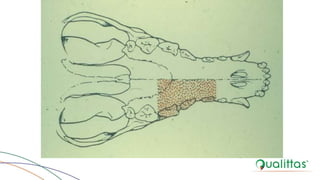

Mandibulectomia do Corpo Rostral

Unilateral

BOJRAB, 1996.

JOHNSON & DUNNING, 2005.

Bilateral

Mandibulectomia do CorpoRostral Unilateral BOJRAB, 1996.

Mandibulectomia do CorpoRostral Unilateral JOHNSON & DUNNING, 2005.

Mandibulectomia do CorpoRostral Bilateral BOJRAB, 1996.

Mandibulectomia do CorpoRostral Bilateral JOHNSON & DUNNING, 2005.

Mandibulectomia do CorpoHorizontal Segmentar BOJRAB, 1996.